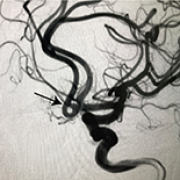

12 Nov 2018 : Clinical Research

Clinical Study on Complications of Intracranial Ruptured Aneurysm Embolization by Stent-Assisted Coil

Yinlong Liu, Jianren Wang

DOI: 10.12659/MSM.911773

Med Sci Monit 2018; 24: CLR8115-8124